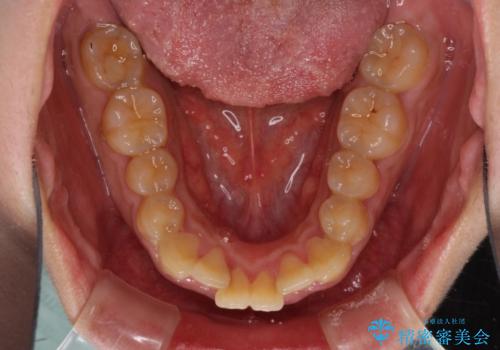

- 口元の突出感と上下前歯のでこぼこを気にして来院された患者様です。

上下前歯部叢生のスペース獲得のため、上下顎左右小臼歯各1歯(計4本)を抜歯して、矯正治療を行うこととしました。

口腔内の清掃性に問題があり、虫歯のリスクが極めて高かったため、短期で治療を終えることを最優先に治療を進めました。